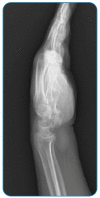

Hydatid Cyst in the Hand